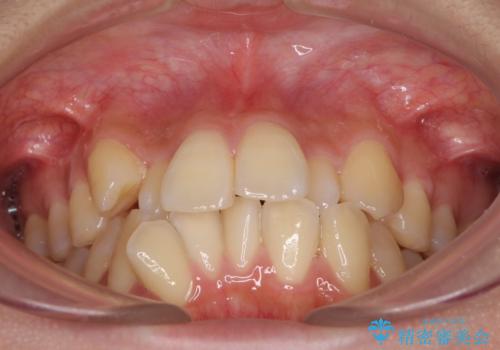

- 前歯のデコボコやクロスバイトと上顎の前突感による口の閉じにくさを気にして来院された患者様です。

目立たない装置を希望されたので、上顎が裏側装置のハーフリンガルを選択し、上下左右の小臼歯(計4歯)を抜歯して矯正治療を行うこととしました。